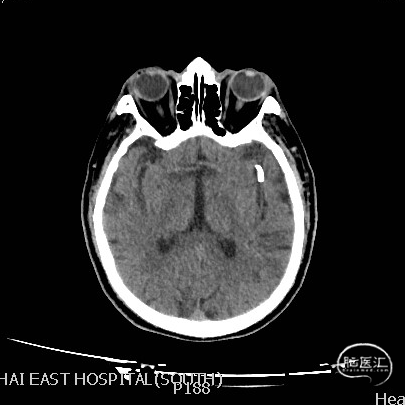

现病史:患者2024.6.6 15:00突发言语不利伴右侧肢体活动障碍,17:00就诊于急诊神经内科,行头颅CT未见出血,立即予以静脉溶栓治疗后症状未缓解。完善头颅CTP提示左侧大脑中动脉M2段狭窄,为责任血管,存在低灌注区,附见一动脉瘤。

复查CT及CTP:未见出血及低灌注区。